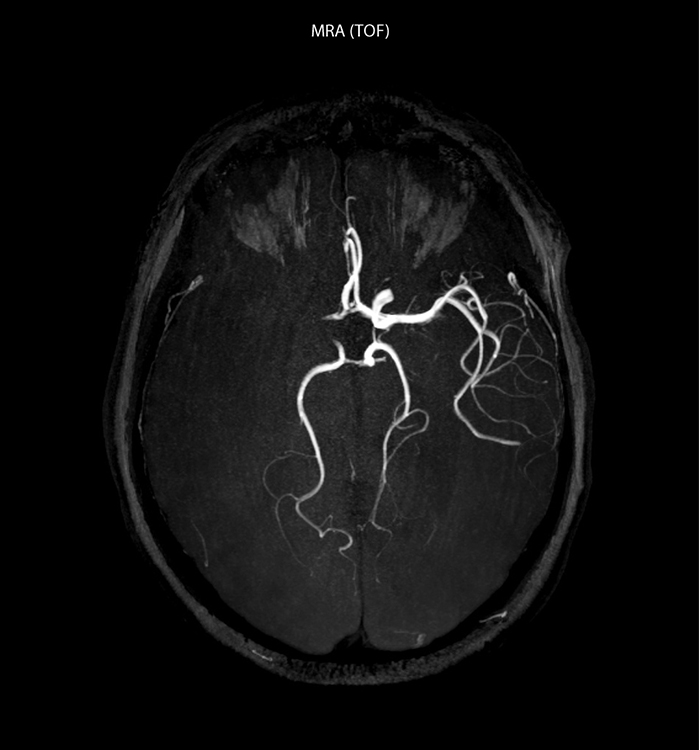

„In Frankreich werden Schlaganfälle in der Regel per MRT und nicht per CT untersucht, auch bei der Notfallbehandlung.“ „In Frankreich erfolgt die Bildgebung bei Schlaganfällen in der Regel per MRT, nicht per CT, auch bei der Notfallbehandlung. Das liegt daran, dass wir mit der MRT eine Ischämie in der akuten Phase direkt darstellen, aber auch Differenzialdiagnosen wie MS und Hämatom ausschließen können. Außerdem ist es uns möglich, die intrakraniellen und extrakraniellen Gefäße im Laufe derselben Untersuchung zu beurteilen“, sagt Dr. Savatovsky.

„Ingenia bietet eine große Flexibilität bei der Parametereinstellung, d.h., wir können eine Sequenz beliebig abstimmen“, erklärt Dr. Savatovsky. „Bei einer Schlaganfalluntersuchung nutzen wir zum Beispiel eine FLAIR-Sequenz von etwa zwei Minuten anstelle der vierminütigen Sequenz, die wir bei MS verwenden. Die Diffusionsbildgebung dauert 30 Sekunden, der T2*-gewichtete Scan ebenfalls 30 Sekunden und die Scan-Dauer bei der Angiographie beträgt weniger als eine Minute. Ingenia ist in dieser Situation ein großartiger Scanner. Auch bei diesen schnellen Sequenzen erzielen wir hochwertige Bilder mit einem guten Signal-Rausch-Verhältnis. Wenn wir anhand der ersten Sequenz feststellen, dass es sich nicht um einen ischämischen Schlaganfall, sondern um einen hämorrhagischen Schlaganfall handelt, können wir zu einer zeitaufgelösten Angiographie wechseln, um nach vaskulären Malformationen und einer Venenthrombose zu suchen.“

„Jede Klinik arbeitet anders, aber für mich umfasst das ideale Schlaganfallprotokoll die diffusionsgewichtete Bildgebung, die FLAIR- und die schnelle suszeptibilitätsgewichtete Bildgebung“, sagt Dr. Savatovsky. „Unsere schnelle suszeptibilitätsgewichtete Bildgebung dauert nur 50 Sekunden, sie ist also genauso schnell wie die T2*-gewichtete Bildgebung. Damit werden Blutungen, aber auch Koagulationen dargestellt. Wir führen zusätzlich eine 3D-MR-Angiographie durch, die Informationen über zervikale und zerebrale Gefäße liefert. Wenn die Patienten keine sofortige Behandlung benötigen oder wenn zusätzliche Informationen erforderlich sind, um über die Therapie zu entscheiden, nehmen wir außerdem eine Perfusionsbildgebung und eine T1-gewichtete Postkontrastbildgebung vor.“